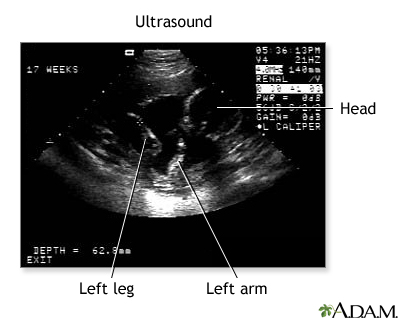

Prenatal ultrasound - series